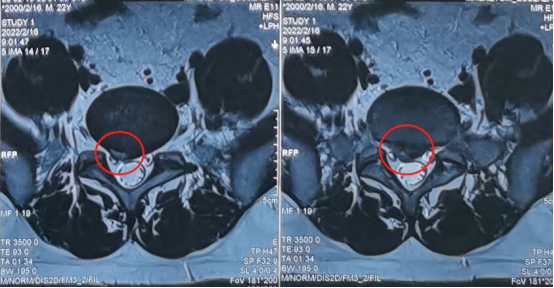

术前影像学资料

陕西冶金医院神经脊柱科的张少华主任、熊东主任接诊后,为小孙进行了详细的查体,并结合各项检查结果和影像学片子,发现他在腰5/骶1节段出现了比较严重的腰椎间盘突出,并造成较为严重的神经受压。